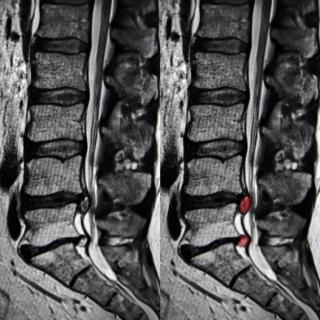

(Слева) Сагиттальный срез, Т1-ВИ: объемное образование вида «цветной капусты», характеризующееся гетерогенной интенсивностью сигнала, исходящее из левого дугоотростчатого сустава L5-S1. Гиперинтенсивность Т1 -сигнала отражает элементы костного мозга.

(Слева) Аксиальный срез, Т1-ВИ: крупная остеохондрома, исходящая из остистого отростка L4, центральное костномозговое пространство характеризуется гиперинтенсивностью сигнала, периферический хрящевой колпачок гипоинтенсивен. В области правого подвздошного гребня видна остеохондрома более классического вида «цветной капусты».

(Справа) Аксиальный КТ- срез, пациент с ВМЭ: визуализируется небольшой костный вырост в области левого корня дуги позвонка с признаками кортико-медуллярной непрерывности с подлежащей костью.